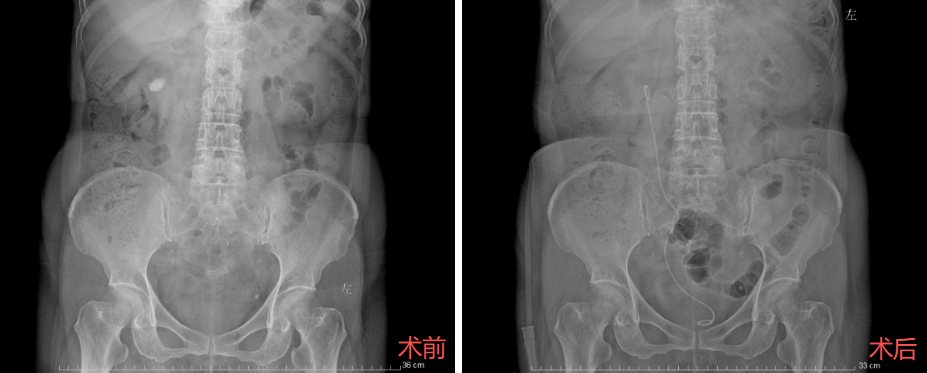

家住王家湾的张女士,则就近前往了位于十里铺的西院区。检查结果显示,患者右侧输尿管下段结石,合并右肾多发结石,最大一颗直径约20毫米。此类结石若拖延治疗,极易引发肾积水或感染等并发症。针对张女士的病情,泌尿外科团队决定实施全麻下输尿管软镜碎石取石术,手术由蒋冠军医师主刀。